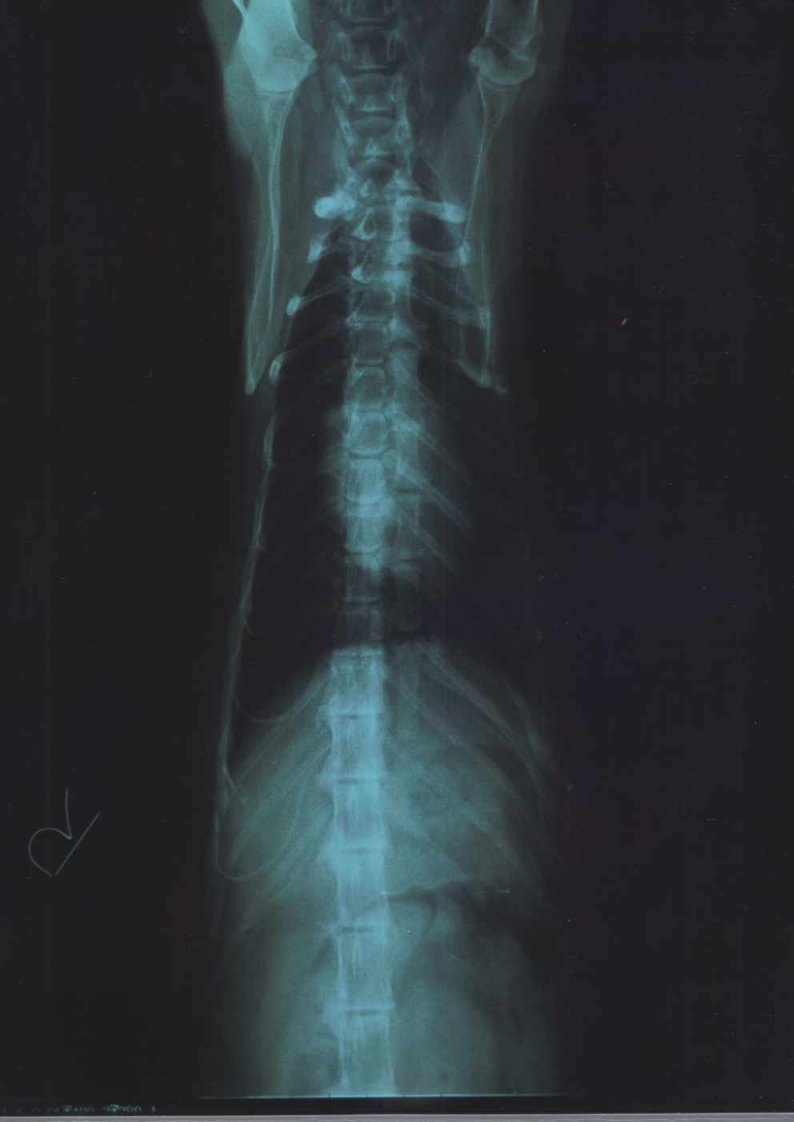

■レントゲン

心臓は見た目さほどバレンタインハートとまでの逆三角形にはみられない

特別大きな心臓というサイズでもなさそうである

肺に水の溜まりも見られず 異常もなし

お腹の異常なし

写真全体をみて 出来物等もなく異常もみられず

ただし 背骨の変形(老齢性によるものと判断)が4月の写真に比べ

ほんの少し進行あり

痛みを伴う状況でないかぎり処置のしよう無し